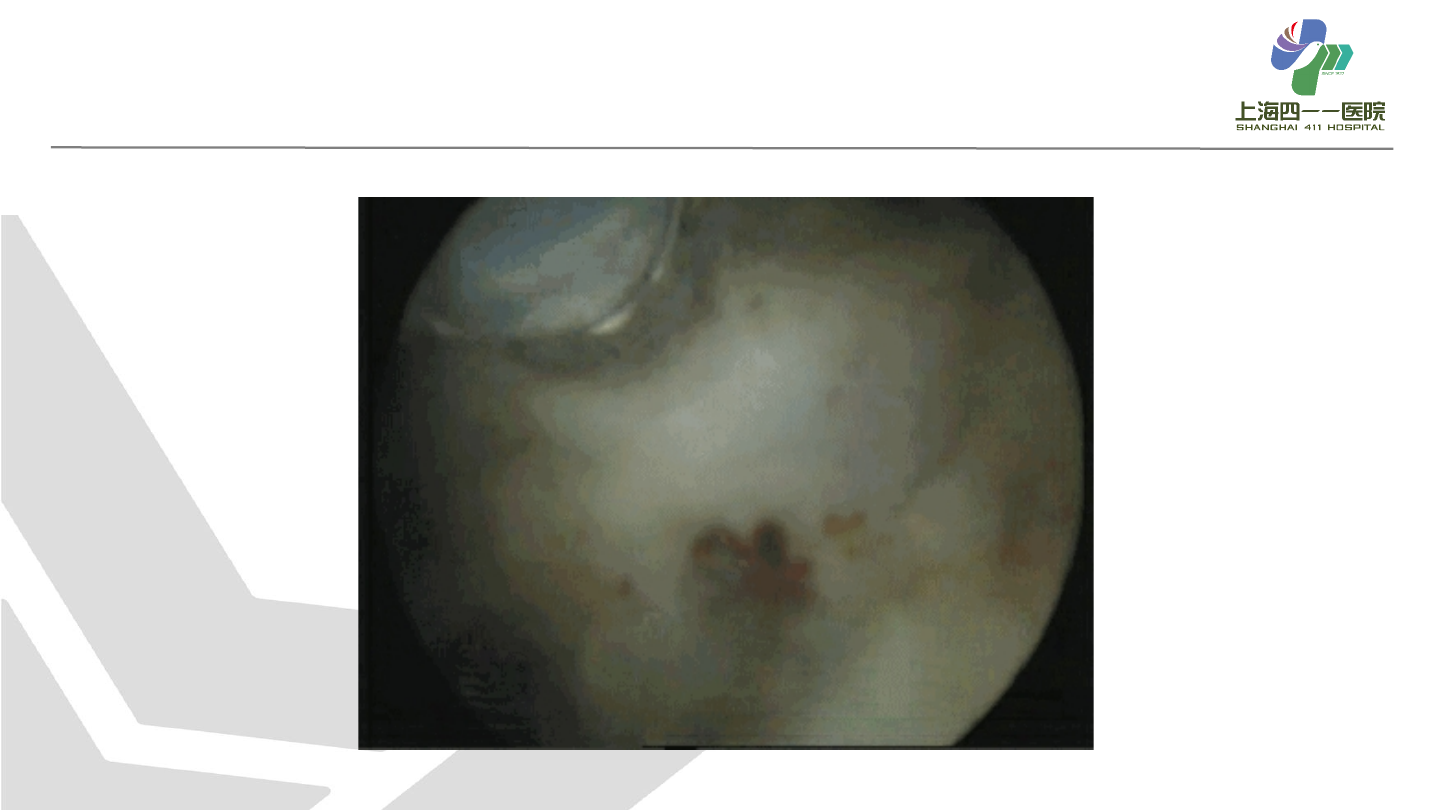

术式

经尿道前列腺电切

术(

TURP

,⾦标准)